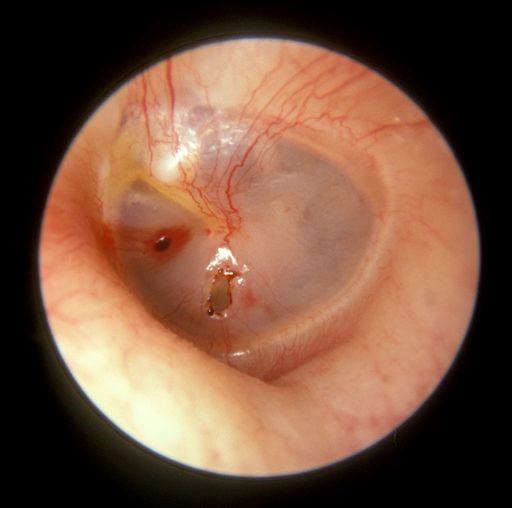

Perforation de la membrane tympanique

Par Michael Hawke MD (Won work), CC BY 4.0via Wikimedia Commons